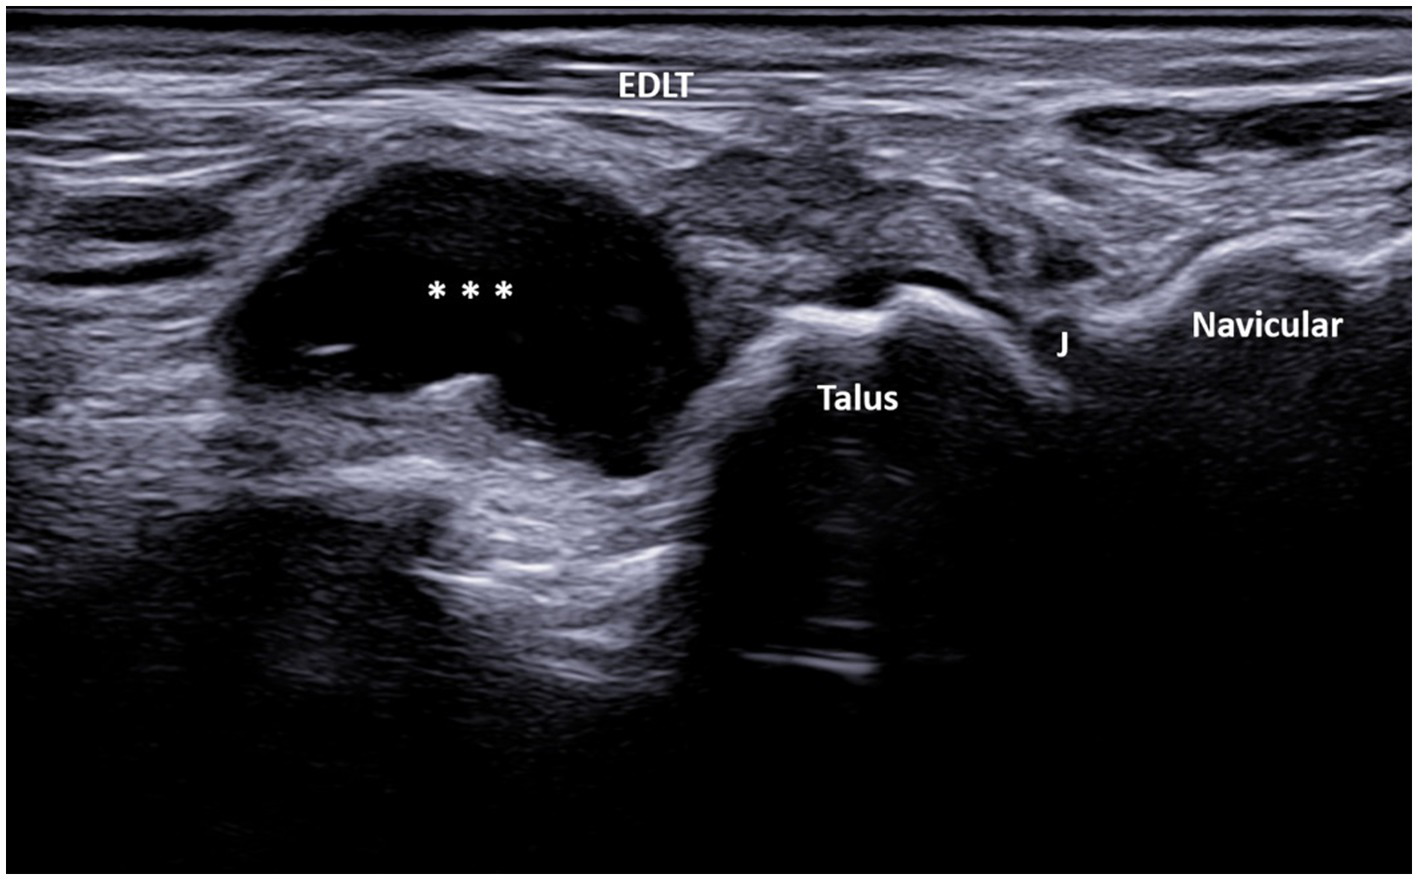

Figure 4

A 67-year-old patient with osteoarthritis. Ultrasound image showing GB with the transducer positioned in the long axis of the foot (left side is proximal). The longitudinal ultrasound image of the dorsolateral ankle reveals an anechoic unilocular fluid collection (***) between the extensor digitorum longus tendon (EDLT) and the talus. J, talonavicular joint and EDLT, extensor digitorum longus tendon.

In the longitudinal plane, the GB had an ellipsoid shape and was located between the EDL tendon and the talus (Figure 4). Its middle portion was the thickest, while the inferior and superior poles narrowed sharply. We did not notice synovial hypertrophy in any recorded bursae. PD signals were registered in only four cases (Figure 5, Supplementary Video 2). Due to the small number of the PD-positive bursitis cases, the exact pattern (i.e., internal or along the bursal wall) and grade of the signal were not analyzed separately.

In our study, the GB was identified using MSUS as a structure distinct from both the tibiotalar and talonavicular joints, extending from the sinus tarsi along the inferior extensor retinaculum to the inferior surface of the EDLT, with varying sizes. The epicenter of the fluid collection, i.e., its thickest part, was always between the EDLT and the dorsolateral talus. In the longitudinal plane, the GB had an ellipsoid shape and was located between the EDL tendon and the talus (Figure 4). Its middle portion was the thickest, while the inferior and superior poles narrowed sharply. The margins of the bursa were well-defined in both the transverse and longitudinal planes, and it was clearly distinguishable from the EDLT, talonavicular joint, and tibiotalar joint.